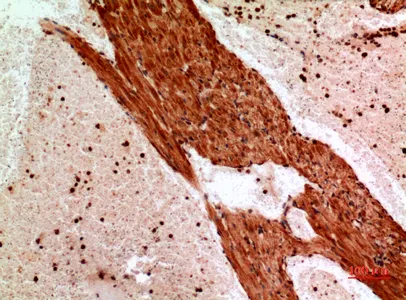

CD235a Rabbit Polyclonal Antibody

Cat: APRab08295

Size1:50μl Price1:$118

Size2:100μl Price2:$220

Size3:500μl Price3:$980